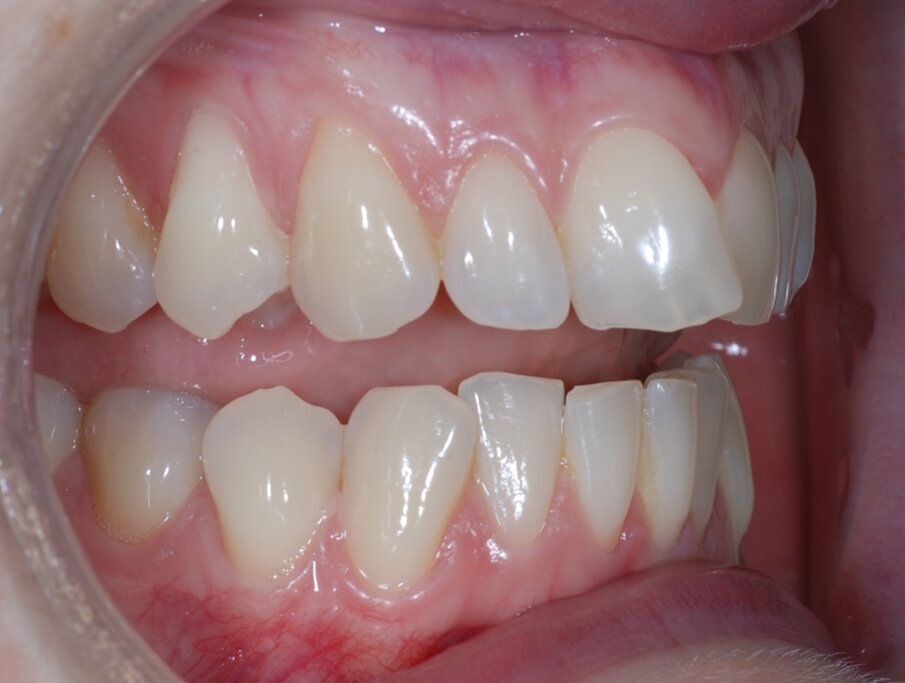

Fig. 1: Pre treatment anterior

Fig. 2: Pre treatment right lateral

Fig. 3: Pre treatment left lateral

Fig. 4: Pre treatment retracted right lateral open bite

Fig. 5: Pre tretament retracted right lateral